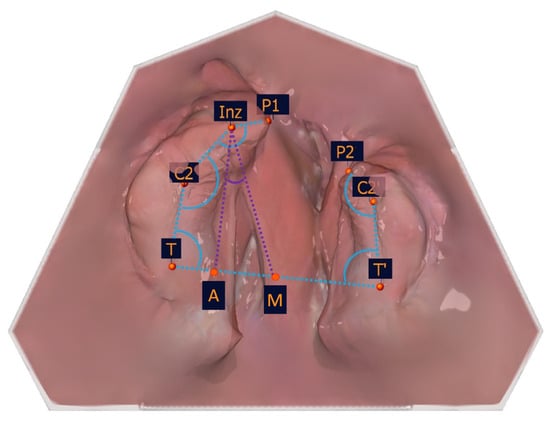

The selection of the measuring points detailed in Table 1 was based on a number of factors, including the publications of Mazaheri et al. [18], Ashley-Montagu [19], Sillman [20], and Robertson [21]. If a point appears on both jaw segments, a ′ indicates that the point is located on the smaller jaw segment. Figure 4 and Table 1 show the measuring points on a dental left-sided cleft lip and palate model.

To identify the transversal landmarks, the large and small segments were divided into the subsegments (T-C2, C2-Inz, and Inz-P1 for the large segment and P2-C2′ and C2′-T′ for the small segment). The most vestibular and most palatal points in each section were determined (Table 2, Figure 5).

Figure 4. Illustration of the anatomical measuring points. The anatomical measuring points and their description are presented in Table 1.

Figure 5. Illustration of the segmental width measuring measurement points of the partial jaw segments. The segmental width measurement points and their description are presented in Table 2.